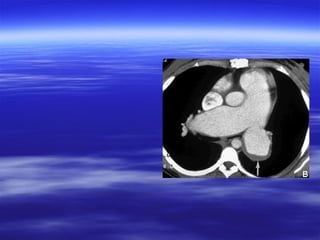

CT findings ooff aaccuuttee ppuullmmoonnaarryy

eemmbboolliissmm

VVaassccuullaarr aabbnnoorrmmaalliittiieess::

 IInnttrraalluummiinnaall ffiilllliinngg ddeeffeeccttss tthhaatt ffoorrmmss aann aaccuuttee

aannggllee wwiitthh tthhee vveesssseell wwaallll && mmaayy bbee ssuurrrroouunnddeedd

bbyy ccoonnttrraasstt mmaatteerriiaall ((ppoolloo mmiinntt ssiiggnn oorr rraaiillwwaayy

ssiiggnn((..

 TToottaall ccuuttooffff ooff vvaassccuullaarr eennhhaanncceemmeenntt..

 EEnnllaarrggeemmeenntt ooff tthhee oocccclluuddeedd vveesssseell..

AAnncciillllaarryy ffiinnddiinnggss::

 PPlleeuurraall bbaasseedd wweeddggee sshhaappeedd aarreeaass ooff iinnccrreeaasseedd

aatttteennuuaattiioonn wwiitthh nnoo ccoonnttrraasstt eennhhaanncceemmeenntt..

CT findings ooffaaccuuttee ppuullmmoonnaarryy eemmbboolliissmm VVaassccuullaarr aabbnnoorrmmaalliittiieess::  IInnttrraalluummiinnaall ffiilllliinngg ddeeffeeccttss tthhaatt ffoorrmmss aann aaccuuttee aannggllee wwiitthh tthhee vveesssseell wwaallll && mmaayy bbee ssuurrrroouunnddeedd bbyy ccoonnttrraasstt mmaatteerriiaall ((ppoolloo mmiinntt ssiiggnn oorr rraaiillwwaayy ssiiggnn((..  TToottaall ccuuttooffff ooff vvaassccuullaarr eennhhaanncceemmeenntt..  EEnnllaarrggeemmeenntt ooff tthhee oocccclluuddeedd vveesssseell.. AAnncciillllaarryy ffiinnddiinnggss::  PPlleeuurraall bbaasseedd wweeddggee sshhaappeedd aarreeaass ooff iinnccrreeaasseedd aatttteennuuaattiioonn wwiitthh nnoo ccoonnttrraasstt eennhhaanncceemmeenntt..  LLiinneeaarr aatteelleeccttaassiiss..